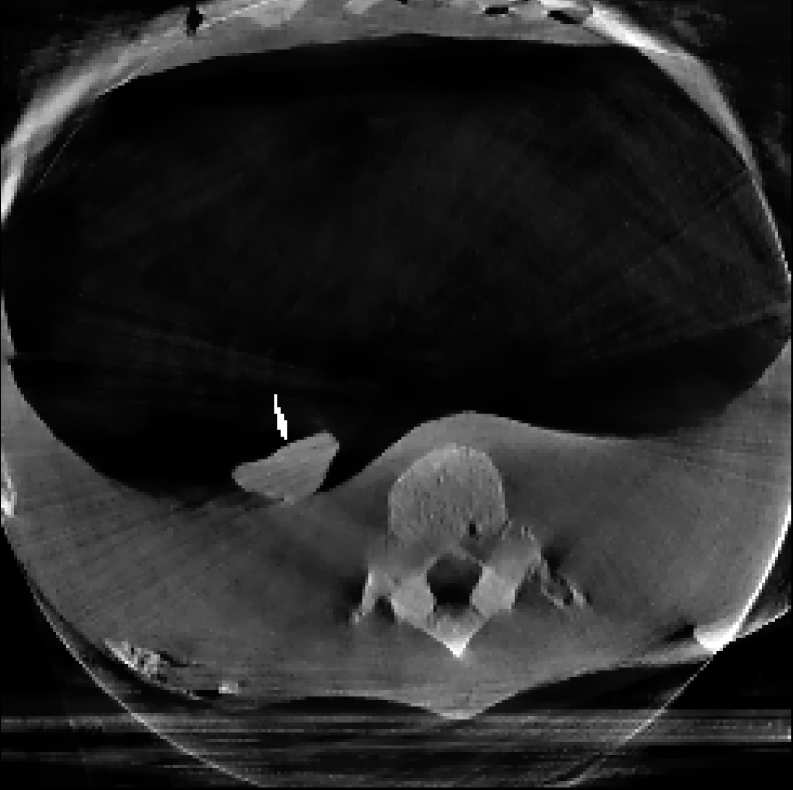

3.2 Lung Needle Surgery Scan:

In this example, we reconstruct a Thorax phantom scanned using the Phillips Allura FD20 Xper C-arm CBCT scanner. This device has source-to-axis and source-to-detector distances of 810 mm and 1195 mm respectively, and an installed detector of size 30×\times40 cm2 with 0.776 mm pixel pitch. Moreover, the data has a resolution of 364×512×364\times 512\timesnumber of projections and the image is reconstructed with a resolution of 256×256×256256\times 256\times 256 voxels.

The reconstructions corresponding to the real-scan data with different number of projections (180, 50, and 20, respectively), can be observed in Figures 3, 4, and 5. In all three figures (a) is the prior image 𝒙p\boldsymbol{x}_{p} used for prior image regularization, (f) is the ground truth image; and the rest of images correspond to different reconstructions (top) with their corresponding errors (bottom). Analogously to the previous experiment, the difference images (or error) should be completely black in the case of a perfect reconstruction and high intensity indicates more inaccurate reconstructions.

Note that the real data contains a lot of measurement noise, and due to the presence of the needle, the reconstructions can suffer from strong metal artifacts. Therefore, the reconstructed images using different algorithms, particularly without explicit regularization, tend to show strong errors even with a high number of projections. Accordingly, all the algorithms with explicit regularization perform better in this scenario, and particularly those including PIPLE or PICCS regularization. Moreover, the proposed IRN-PIPLE algorithm significantly outperforms other methods, and IRN-PICCS is not far behind. Using only TV regularization struggles to separate artifacts from features, oversmoothing images and thus loosing important image features. Notably, the proposed methods reconstruct high quality images in less than 2 minutes in an implementation that is not optimized to solve this specific geometry.

Figure 5: Reconstructed images using real measurements of a thorax phantom with 20 projection. The reconstructed images are shown in [0, 0.03]; difference images in [–0.04, 0.04].